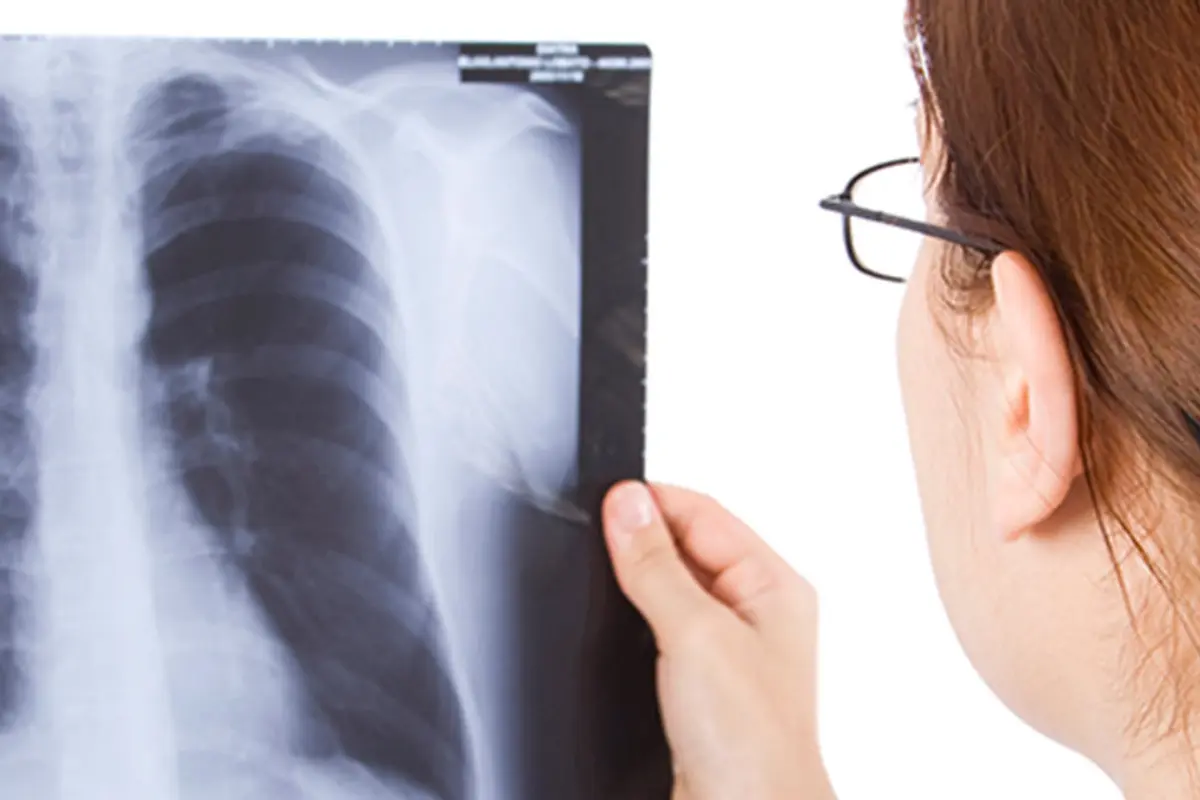

La tuberculosis es causada por una bacteria que afecta principalmente a los pulmones y se transmite por vía aérea. Entre sus síntomas están la tos crónica, fiebre, sudoración nocturna y pérdida de peso. Aunque es curable con tratamiento, puede ser grave si no se atiende oportunamente.